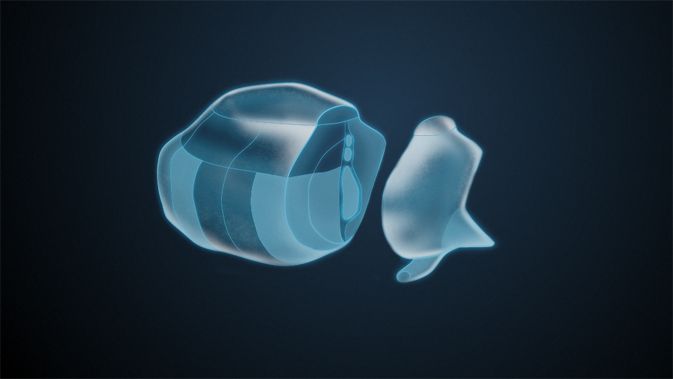

Insellappen

Der Insellappen ist ein eingesenkter Teil des Cortex (Großhirnrinde), der durch Frontal-, Temporal– und Parietallappen verdeckt wird. Diese Überlagerung wird Opercula (Deckel) genannt. Die Insula hat Einfluss auf die Motorik und Sensorik der Eingeweide und gilt in der Schmerzverarbeitung als Verbindung zwischen kognitiven und emotionalen Elementen.

Operculum

Rindengebiete von Frontal-, Schläfen– und Temporallappen an der seitlichen Innenfurche. Das Operculum bedeckt die Inselrinde.